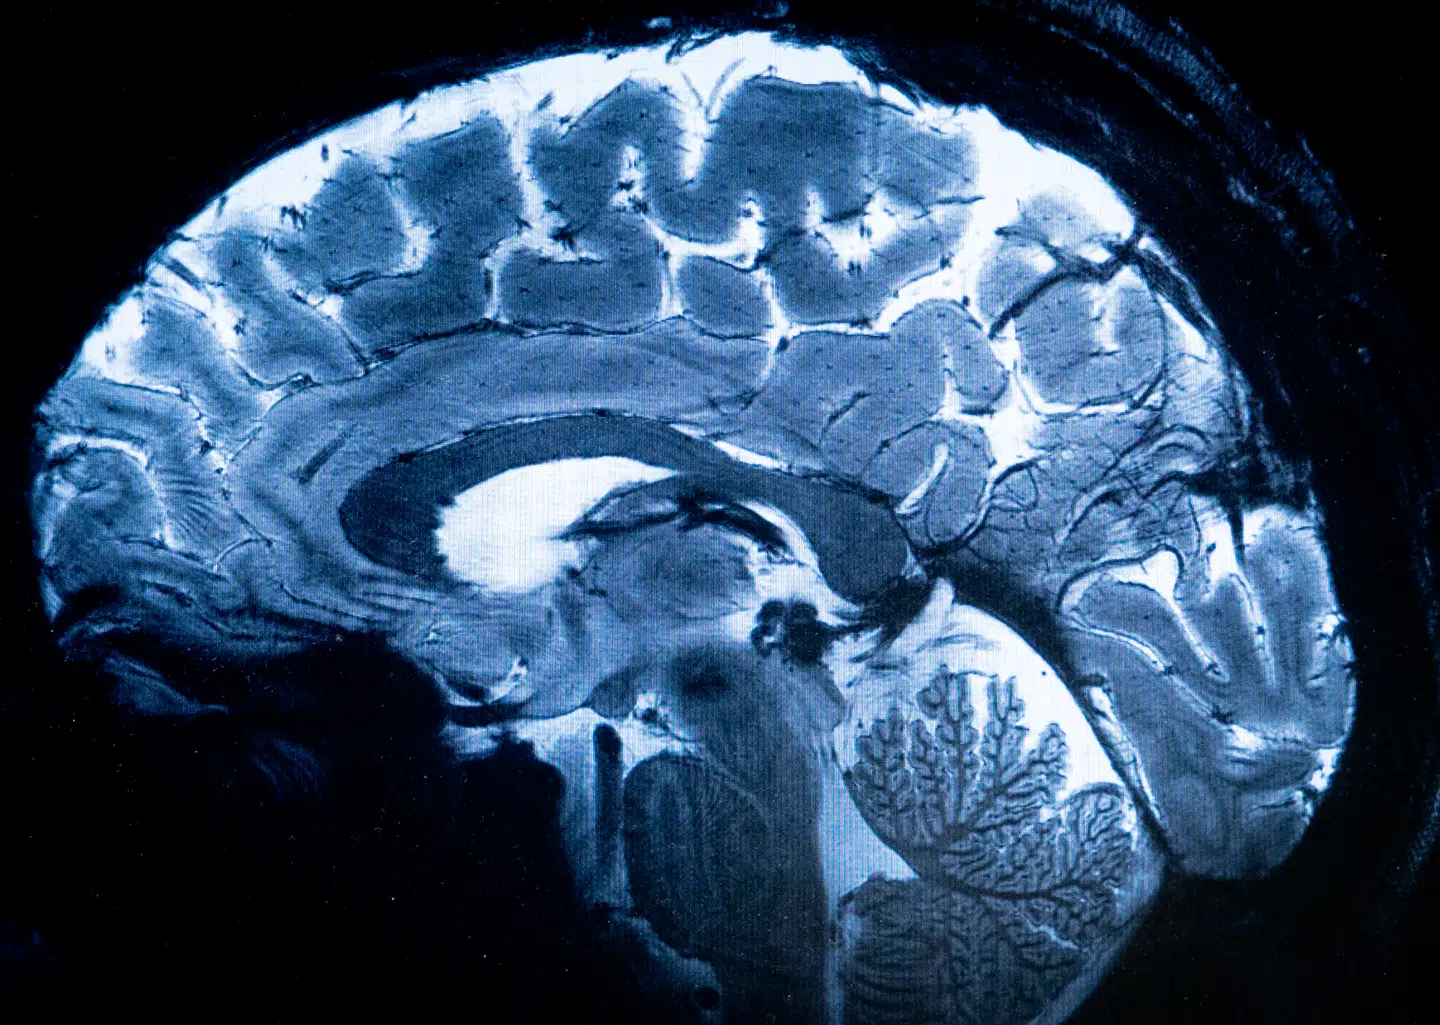

Kloge børn lever længst. Forskere har i mange år vidst, at mennesker, der som børn scorer højt i intelligenstest, ofte lever længere end andre. Man har bare ikke vidst hvorfor.

Forskere i genetik og neurovidenskab analyserede genetiske oplysninger fra over 12.000 personer om deres intelligens som børn samt data fra næsten 390.000 personer om, hvor gamle deres forældre blev. Ved at sammenholde disse oplysninger kunne de beregne en genetisk sammenhæng mellem barndommens intelligens og livets længde.

Forskerne mener, at de nye resultater tyder på, at mennesker med stærke gener får både sunde kroppe og skarpe hjerner og dermed sundere vaner og mere stabile livsforløb. Man vil nu forsøge at kortlægge, hvilke gener der især spiller en rolle, så man på sigt kan hjælpe mennesker, der genetisk set har større risiko for sygdom og tidlig død.